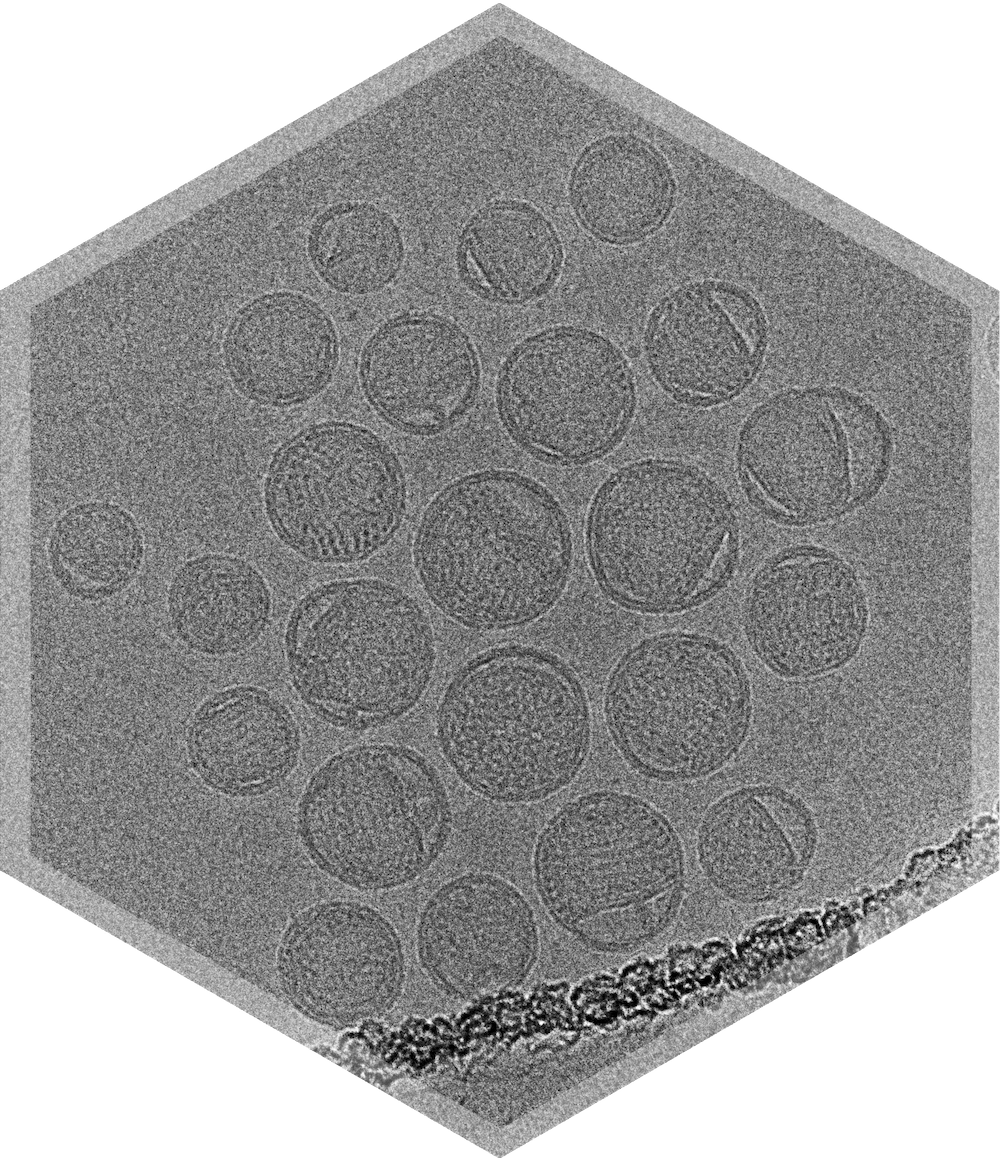

Lipid nanoparticles are increasingly used for drug delivery, however their tendency to be heterogeneous leads to challenges in characterization. Only cryo-TEM provides data on morphology, lamellarity, size distribution, & payload in just one study.

We will perform cryo-TEM screening on our Glacios microscopes for up to 6 LNP samples at a time, at 73kx magnification.